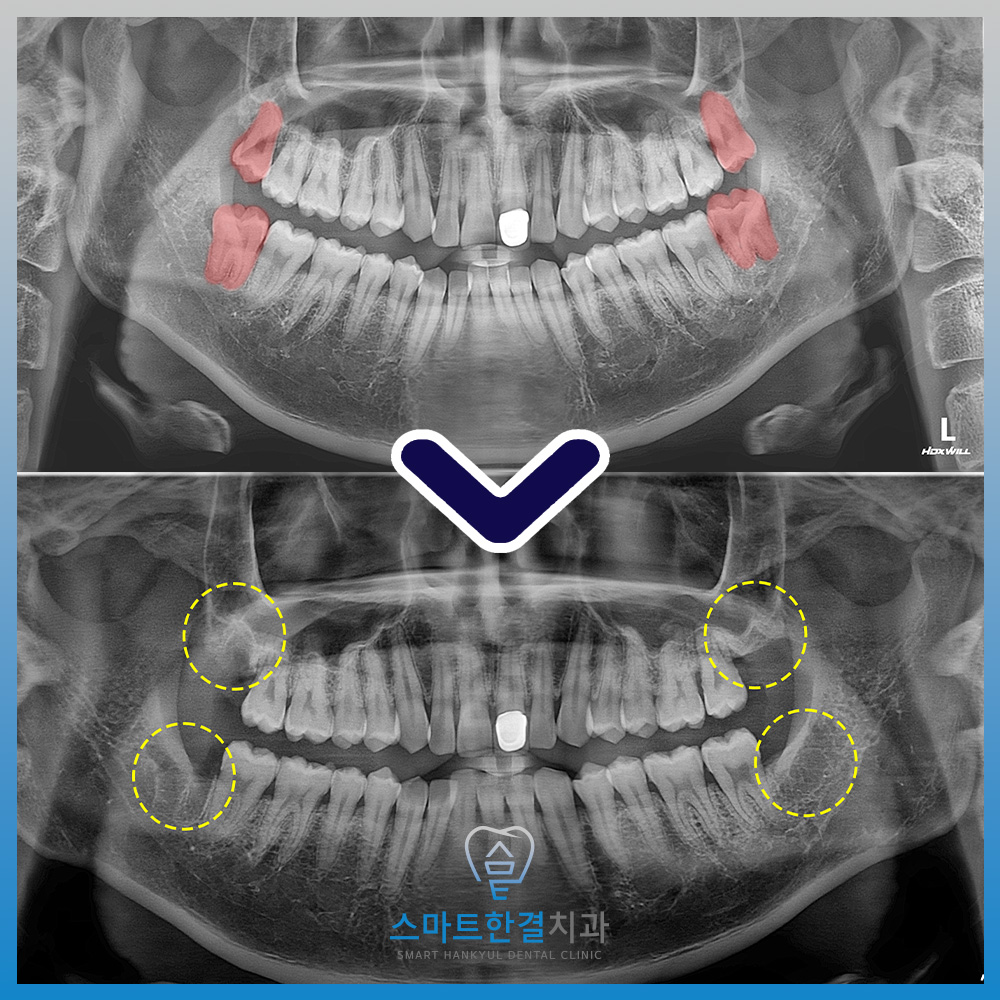

환자분께서는 말씀드린

내용을 이해하시고 먼저 왼쪽부터

발치를 진행했는데요.

사진과 같이 주변 조직의 손상 없이

깨끗하게 발치 한 모습을 볼 수 있었어요.

이후 잇몸이 어느 정도 아물고 난 뒤

오른쪽까지 발치를 하였습니다^^

위쪽 사랑니는 상악동과 가까웠으며,

아래쪽은 신경관과 가까워

상악동 개통 또는 신경관 손상의

우려가 있었으나 화서동치과에서는

치료 전 3D CT를 촬영해 거리와 위치를

확인 후 진행하여 보다 안정적으로

발치를 할 수 있었어요.